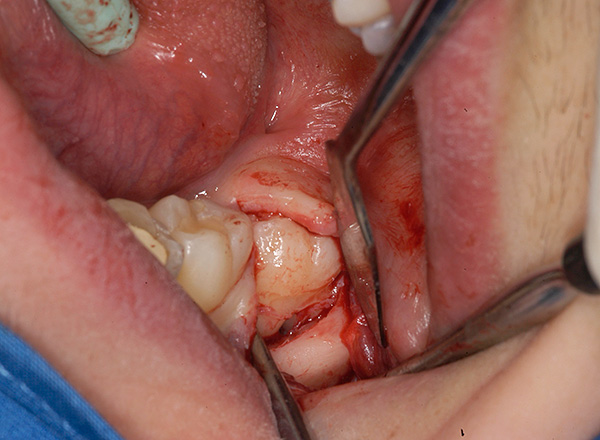

- Estrazione di un dente del giudizio da parte degli elevatori o segatura con frese in parti e eliminazione graduale di ogni pezzo. Non aver paura di tagliare un dente dalla mascella, poiché accelera quasi sempre il lavoro 2-3 volte e ti consente di ottenere un risultato positivo in meno tempo. Rispetto alla segatura, è molto più spiacevole scavare un dente retinato con uno scalpello;